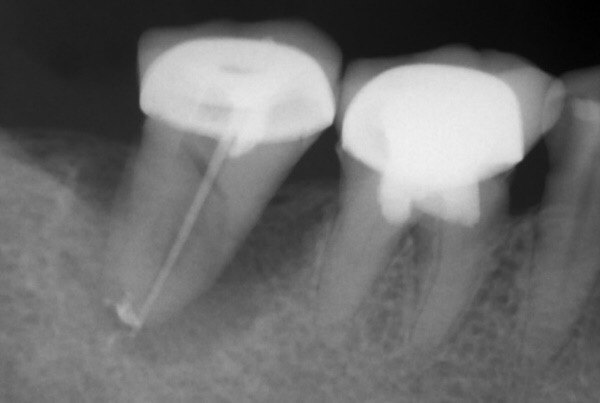

图3: X线:显示牙冠的牙齿牙根纵向折断。处理方法:拔除。、

图1: 金属全冠,牙床红肿、牙周袋形成

图2: X线检查牙做过完善的根管治疗,并且发生根折。